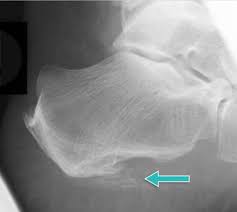

Den gesamten Komplex bilden außerdem Gelenke Fußwurzelgelenke Gelenke der Mittelfußknochen und Zehengelenke viele für die. Eine weitere Ursache für Schmerzen an der Fußaußenseite ist die Fraktur des fünften Mittelfußknochens. Der menschliche Fuß besteht aus 26 Knochen.

Den gesamten Komplex bilden außerdem Gelenke Fußwurzelgelenke Gelenke der Mittelfußknochen und Zehengelenke viele für die. Die Basen der Mittelfußknochen werden darauf mit der Fußwurzelknochenreihe mit Schrauben versorgt. Hühneraugen und Schwielen sind dicke harte Hautpartien die sich häufig an der Seite deiner Füße und Zehen entwickeln. Andere Erkrankungen der Füße entstehen durch Krankheiten die viele Bereiche des Körpers betreffen wie Diabetes mellitus Gicht oder andere Arthritisformen. Den gesamten Komplex bilden außerdem Gelenke Fußwurzelgelenke Gelenke der Mittelfußknochen und Zehengelenke viele für die. Das untere Sprunggelenk verbindet das Sprungbein mit den Knochen der Fußwurzel und dem Fersenbein. Sie unterstützen uns bei der Beantwortung der Fragen welche Seiten am beliebtesten sind welche am wenigsten genutzt werden und wie sich Besucher auf der Website bewegen. Trochanter grch der Rollhügel sd am Oberschenkelknochen. Fuß- und Knöchelbrüche sind recht häufig.